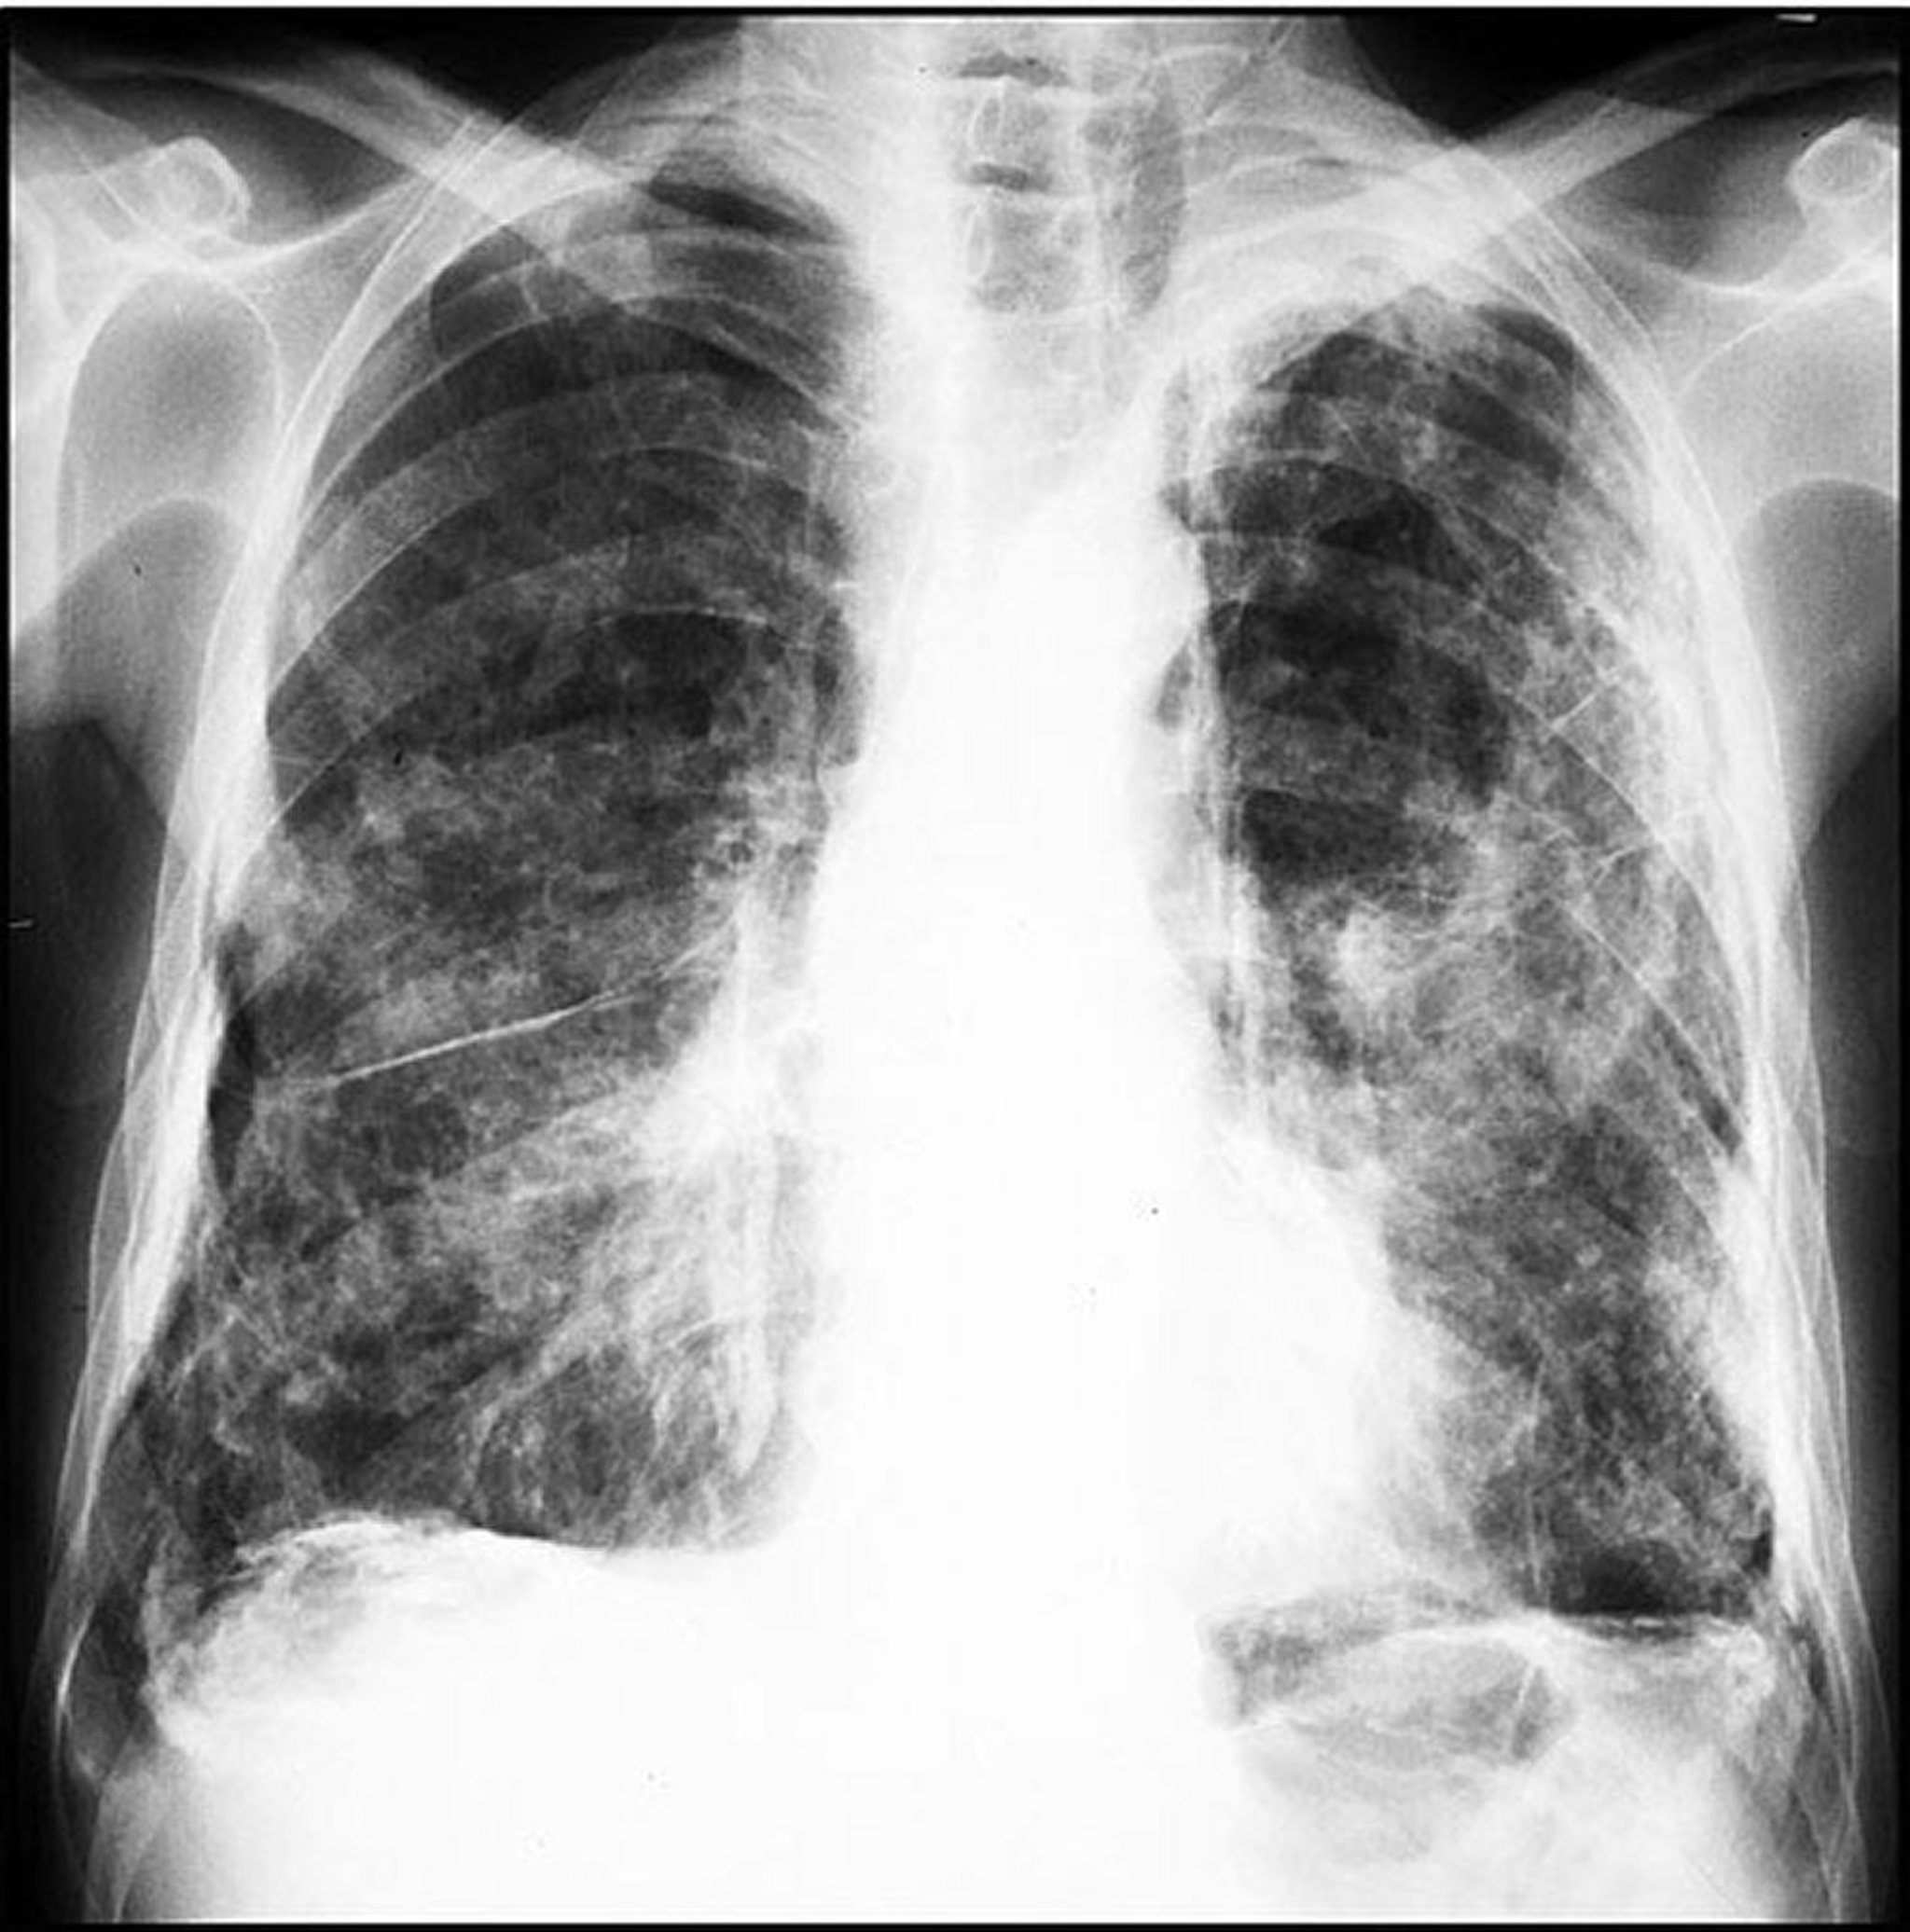

孤立性の胸膜プラークは通常,両側の壁側胸膜および横隔膜に接する領域を侵す。肺尖部および肋骨横隔膜角は侵されない傾向がある。プラークの石灰化がよくみられる。胸部CTにより胸膜疾患を肺実質疾患および胸膜下脂肪と鑑別できる。曝露から胸膜プラークの発生までの潜伏期間は一般に20年以上である。胸膜プラークは有意なアスベスト曝露のマーカーである;したがって,胸膜プラークを有する患者では,他のアスベスト関連疾患が発生しないかモニタリングすべきである。

胸壁および横隔膜の表面に生じた石灰化した胸膜プラーク。

Image courtesy of David W.Cugell, MD.